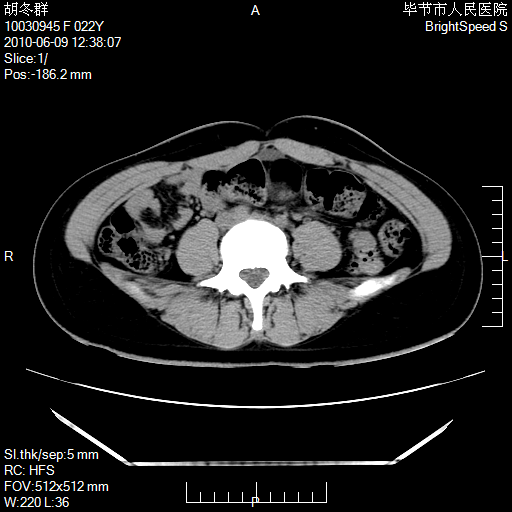

患者23岁,发现腹部包块3月。

盆腔内囊性占位;穿刺或者直接手术拿掉即可,不必紧张。

左侧卵巢囊腺瘤或囊腺癌

盆腔内囊性占位性病变;考虑左侧卵巢囊腺瘤。

有分隔、壁薄,支持考虑左侧卵巢囊腺瘤。

左侧卵巢浆液性囊腺瘤。

支持考虑左侧卵巢囊腺瘤;宫腔积液。

有分隔、壁薄,支持考虑左侧卵巢囊腺瘤。排尿后,膀胱缩小,由于重力作用,肿块下移就到了膀胱位置,很好理解。